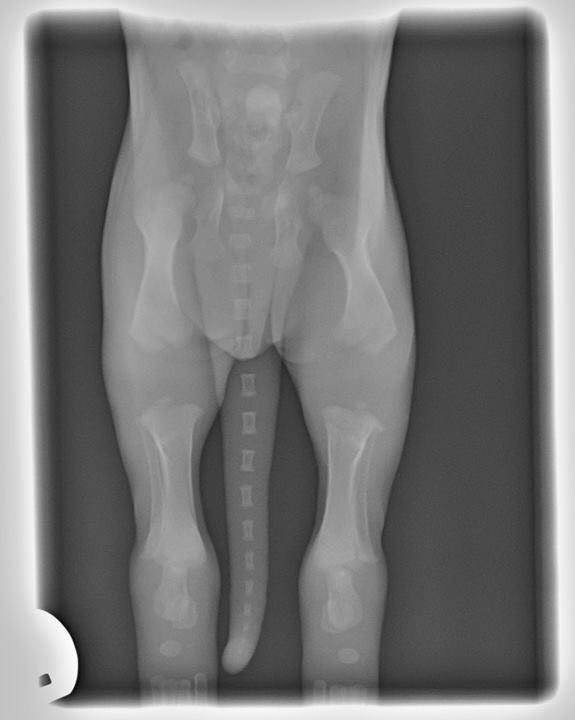

Check out the X-ray image below of a 3 week old puppy.

Look at how far apart the bone growth plates are!

Growth plates are regions of cartilage that sit at the ends of the long bones. The growth plates are vulnerable to being injured and potentially fractured because they are the last portion of the bones to harden are.

This X-ray vividly depicts why you should never permit puppies to jump, walk up/down stairs, over-exercise or over-train. Any type of high-impact activities or prolonged exercise on hard surfaces can potentially stunt the puppy’s bones, cause them to cease growing or grow in a crooked or misshapen way.

A good rule of thumb (Consider it the “Puppy Rule“🐶🐾) is a ratio of 5 minutes of exercise per month of age (up to twice a day) until the puppy is fully grown. For example, 15 minutes (up to twice a day) at 3 months old, 20 minutes when 4 months old, and so on until they are fully grown and can go out for much longer. After the age of 8 months, there is minimal longitudinal growth of bones going on, and by one year of age, most growth plates are fused or closed and no longer show on x-rays (source:Vet Surgery Central).